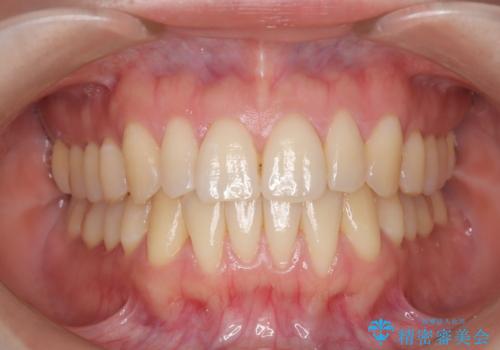

【インビザライン】反対咬合を治したい

- 前歯の反対咬合を主訴に来院されました。

インビザラインにて歯列弓の拡大により叢生の改善を行うことができ、患者様にも満足していただました。

前歯の反対咬合は歯牙への負担も大きくできるだけ早期に治療を行うことを推奨しています。